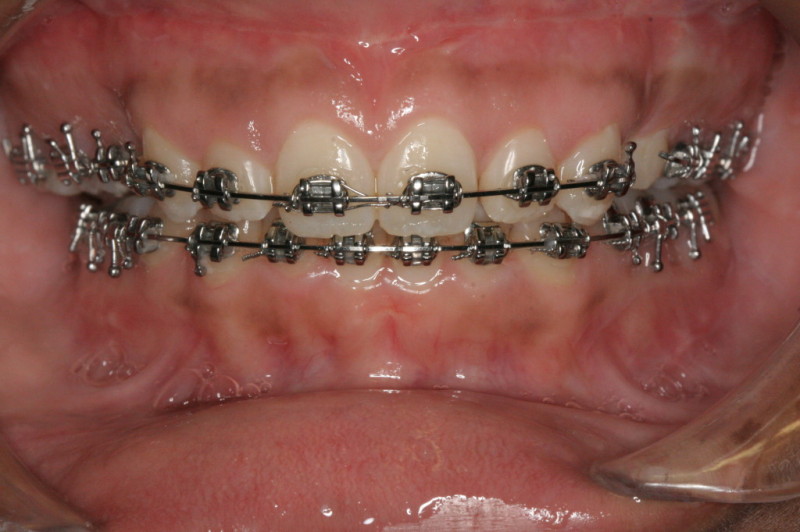

Finished Patient with a Perfect Bite and Excellent Facial Proportions